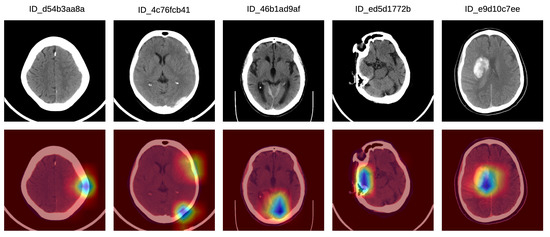

- We provide interpretations explaining the decisions of our model.